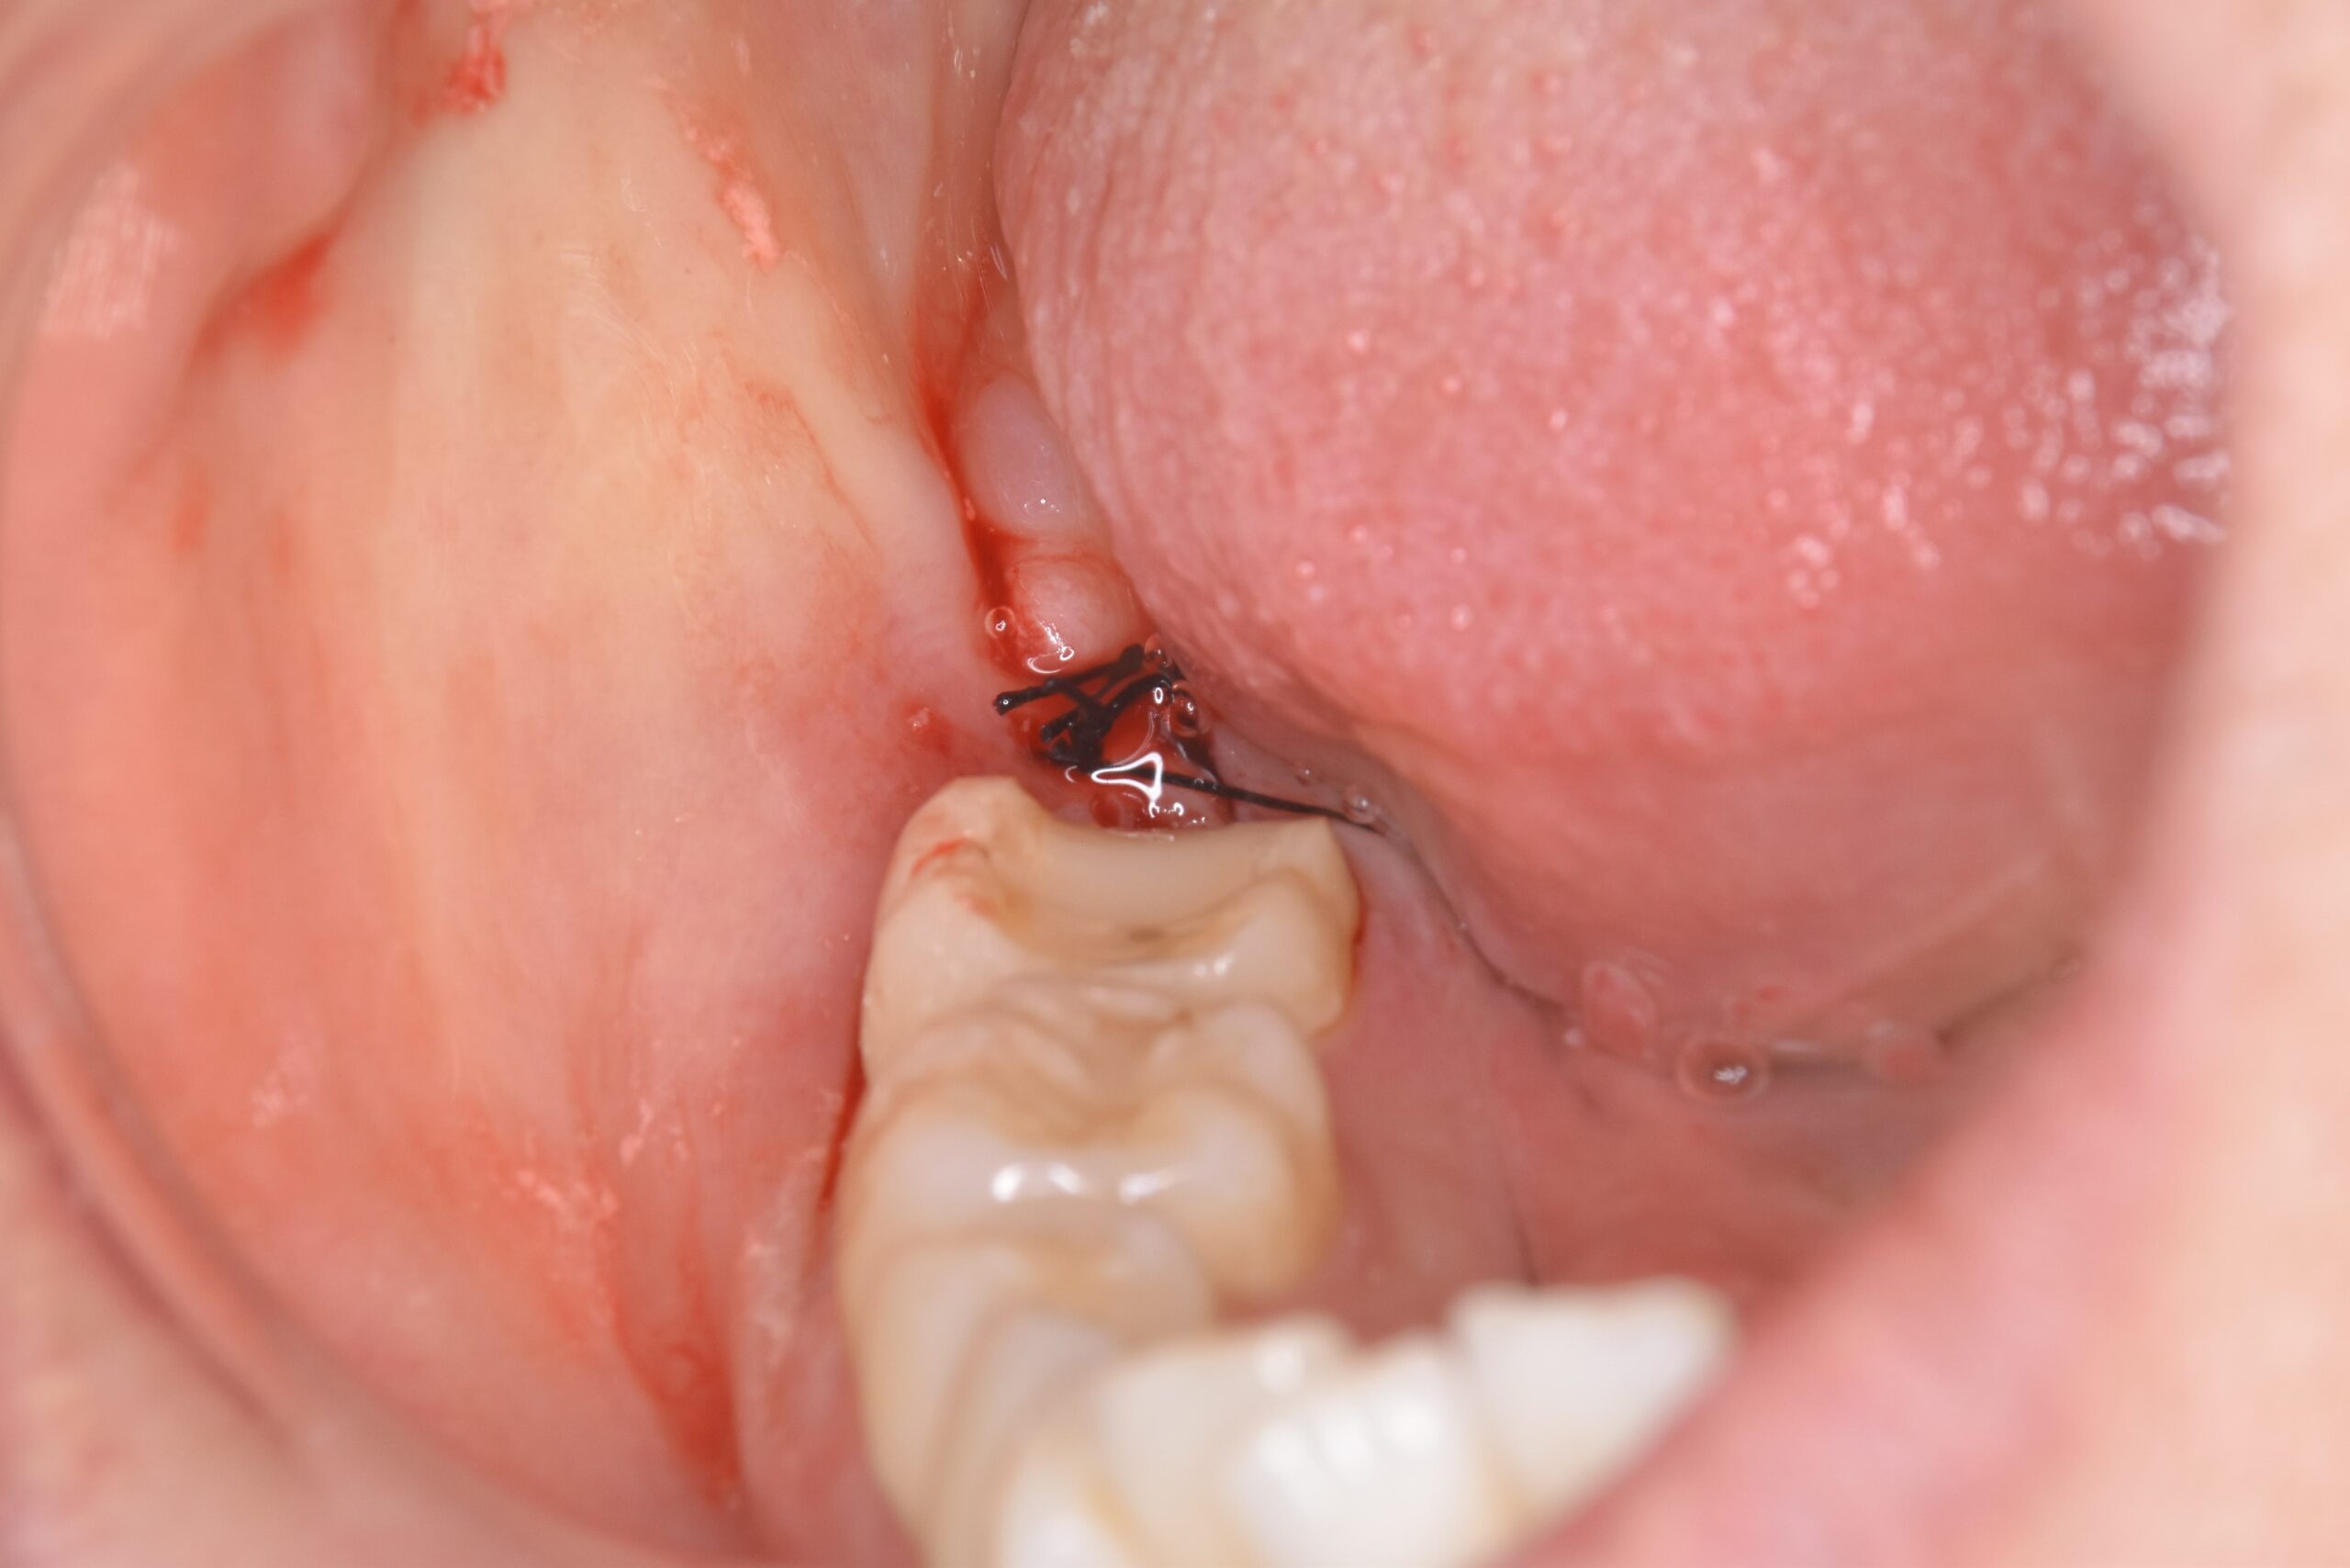

右下奥歯が腫れた 30代男性 親知らずの抜歯

親知らずの周囲の炎症

頭の部分が手前の歯にぶつかっていたので、その部分をカットしてスペースを作ったのち、抜歯をしています。

黒くなっている部分が虫歯で、白くなっているのがプラークと呼ばれる細菌の塊です。歯茎の中にあったので歯ブラシ等では届かないためこのようになったと思われます。